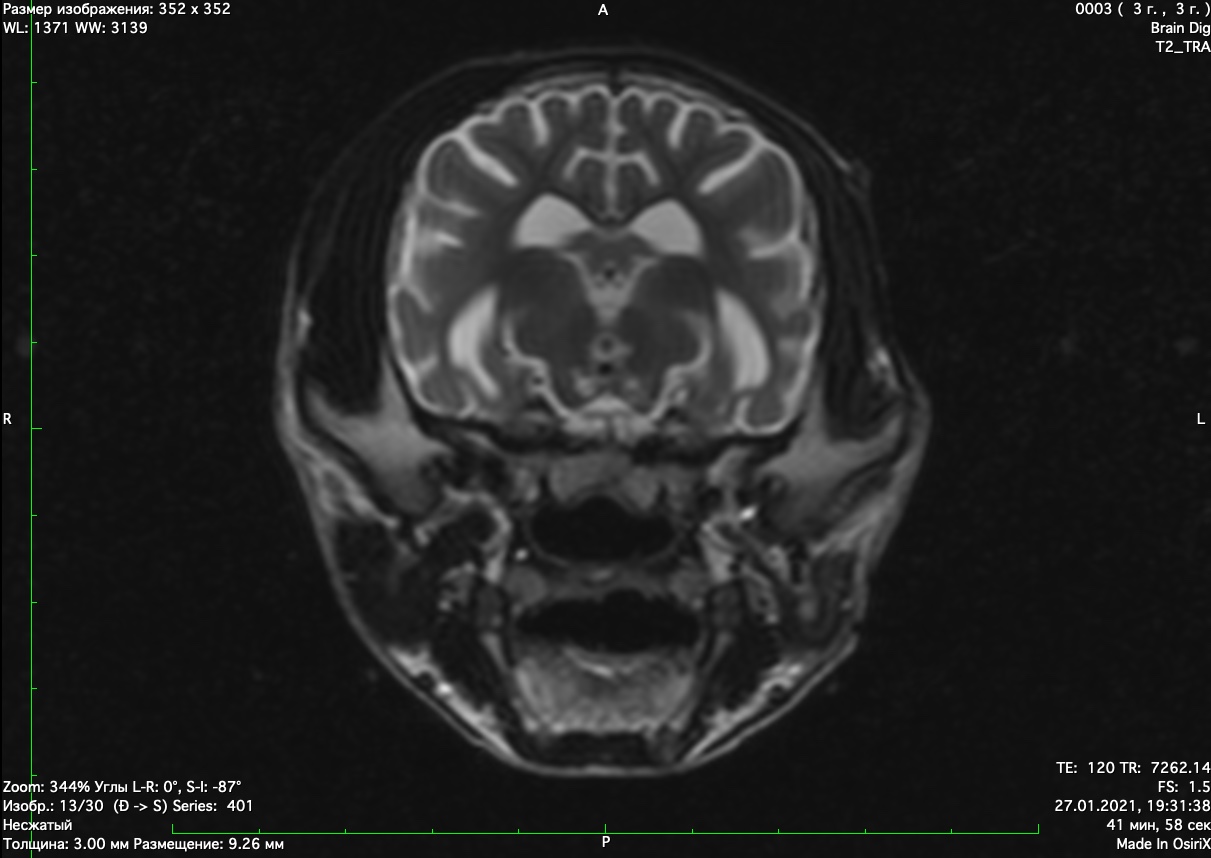

При проведении мрт диагностики установлено признаки атрофии коры голов головного мозга и мозжечка нарушение дифференциации между серым и белым веществом головного мозга. Признаки кровоизлияний в коре головного мозга

Данные изменения характерны для болезней накопления